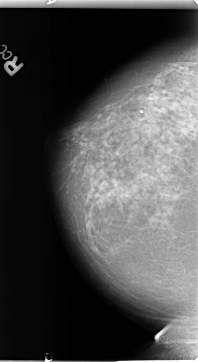

Digital Database for Screening Mammography

Volume: benign_01 Case: B-3131-1

B_3131_1.RIGHT_CC

RIGHT_CC LINES 4704 PIXELS_PER_LINE 2568 BITS_PER_PIXEL 12 RESOLUTION 50 NON_OVERLAY

RIGHT_MLO LINES 4720 PIXELS_PER_LINE 2768 BITS_PER_PIXEL 12 RESOLUTION 50 NON_OVERLAY